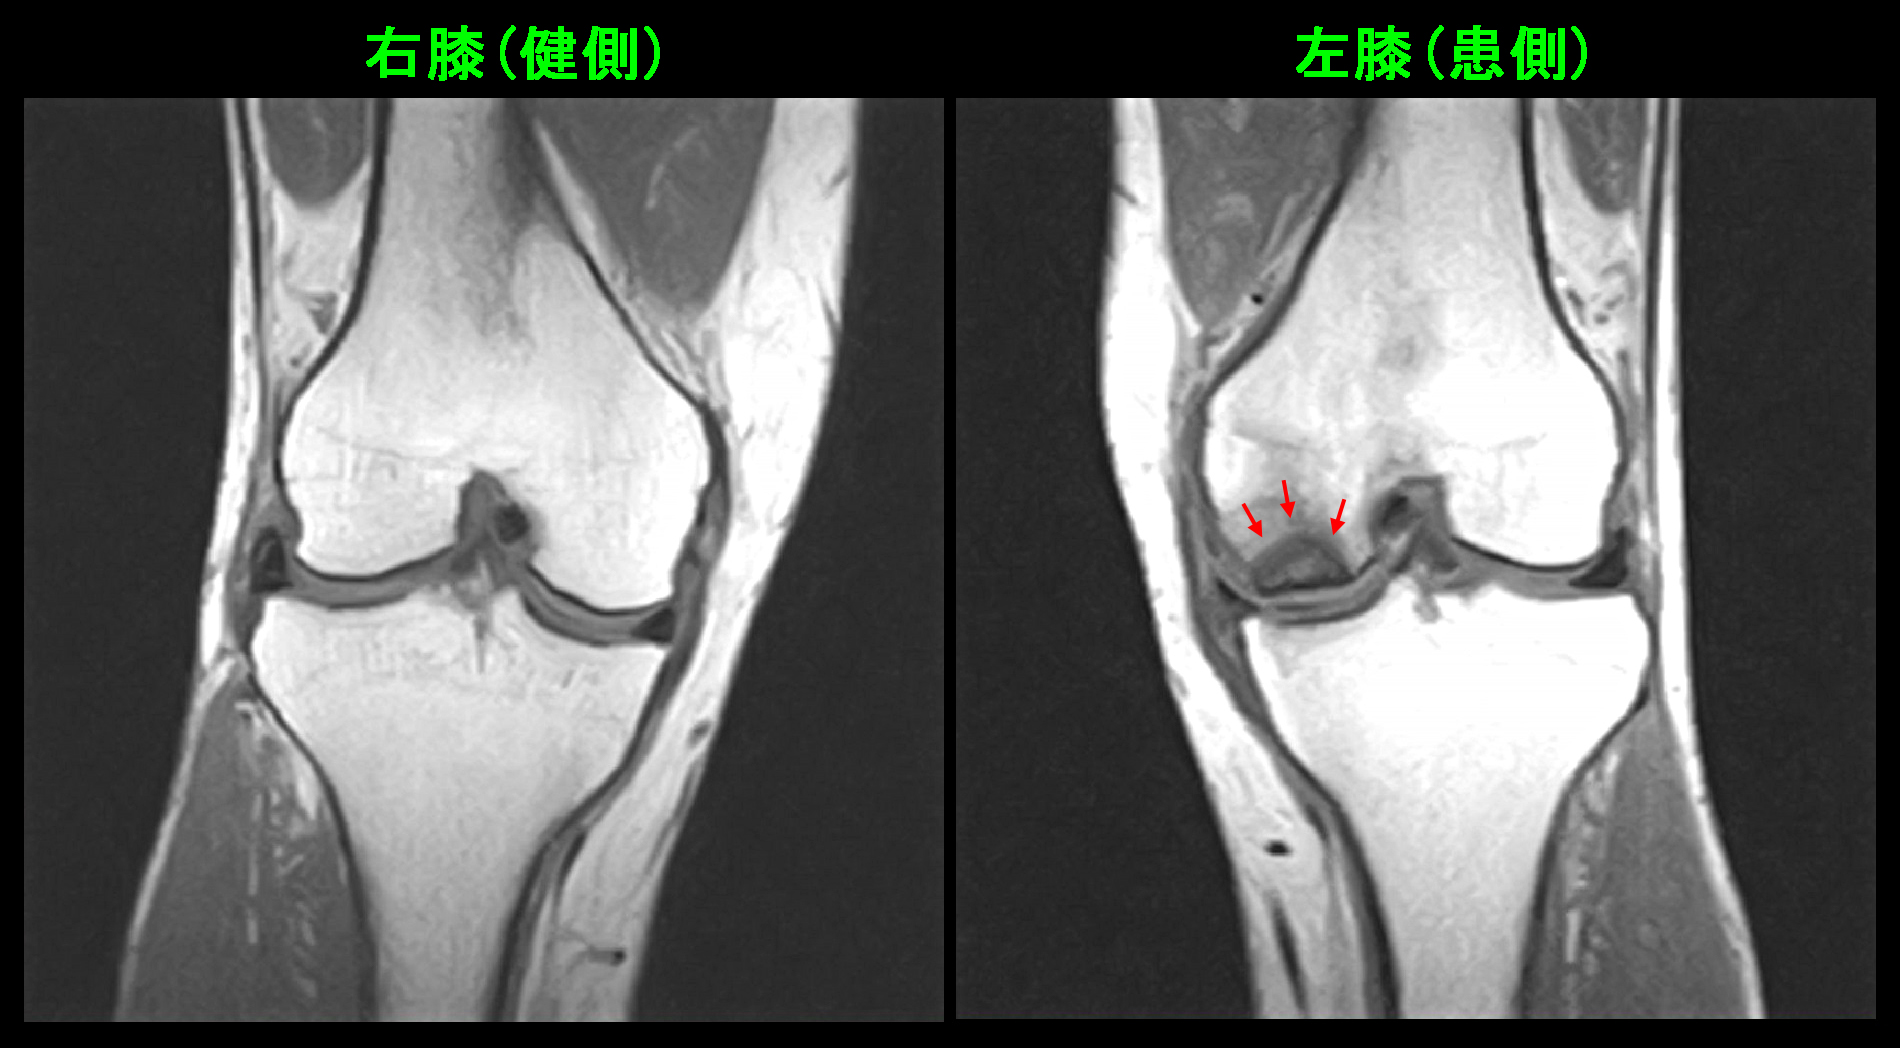

80才 初診時MR.jpg

確かに当院のMRI検査でも左膝の大腿骨内顆部には広範な骨壊死が確認されました。発症したのが2月で当院を受診したのが7月で、発症から5か月が経過しています。私の大腿骨内顆部の骨壊死に対する見解では、順調に治療していれば半年ぐらいで症状が落ち着くことが多いと考えています。この患者さんの場合、5か月が経過しているのですから、順調に経過していれば間もなく症状が落ち着く可能性がある時期です。それを前提に治療を開始しました。